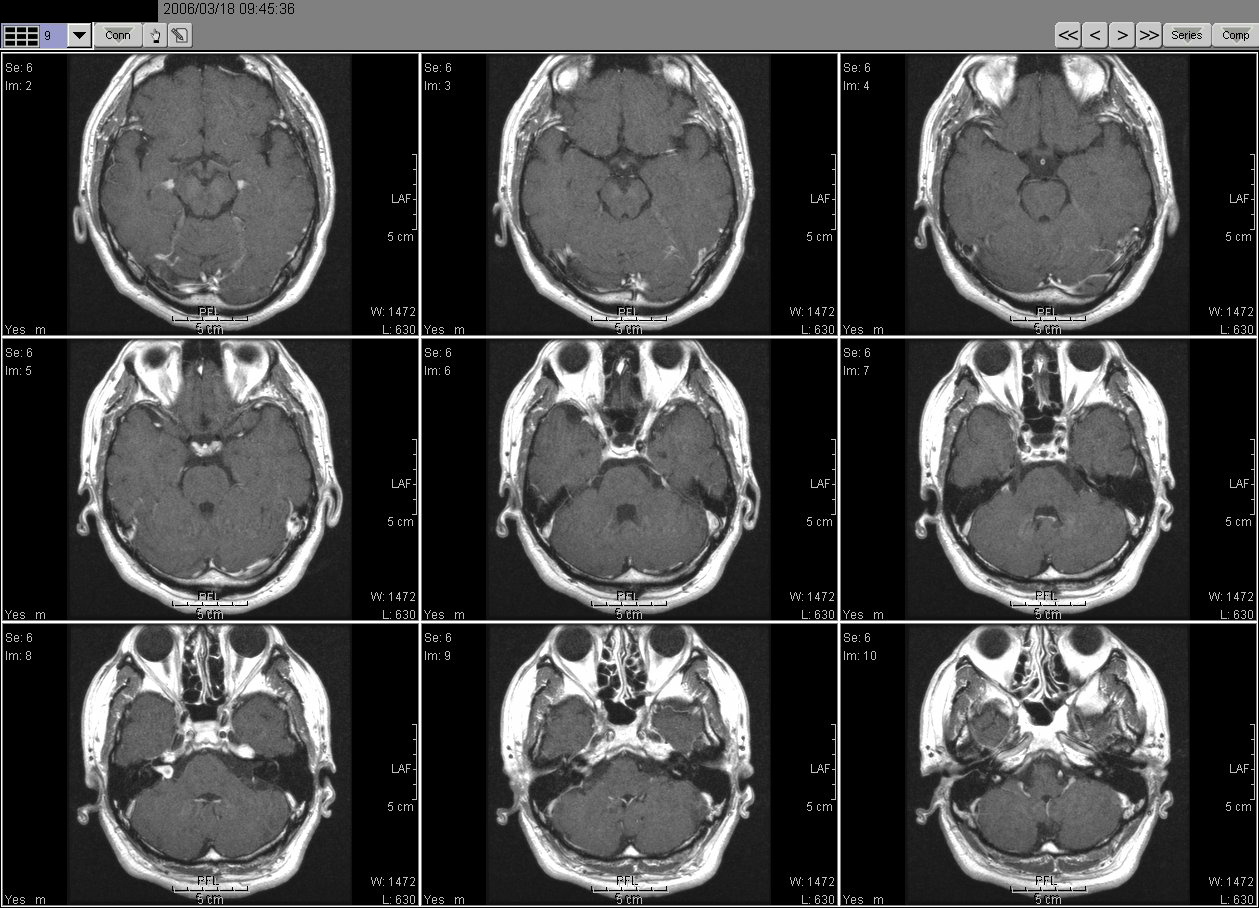

2006_03_18 MRI

2006_03_18MRI01